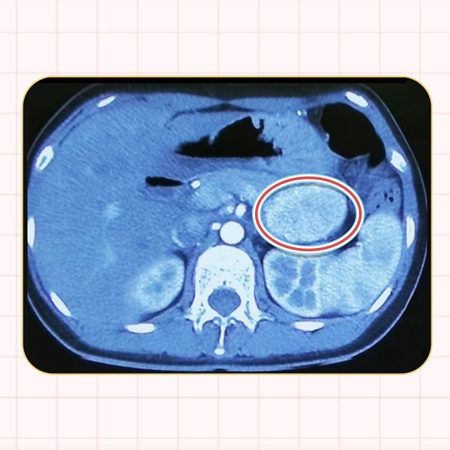

当患者出现临床症状或体检提示占位性病变时,会通过一系列影像学检查如CT和磁共振来初步诊断,这些检查的敏感性大约达到60%。若怀疑为神经内分泌肿瘤,则进一步推荐进行全身奥曲肽显像扫描、68Ga-PET/CT或18F-FDG PET/CT等高级别影像学检查,以获取更精确的诊断信息。